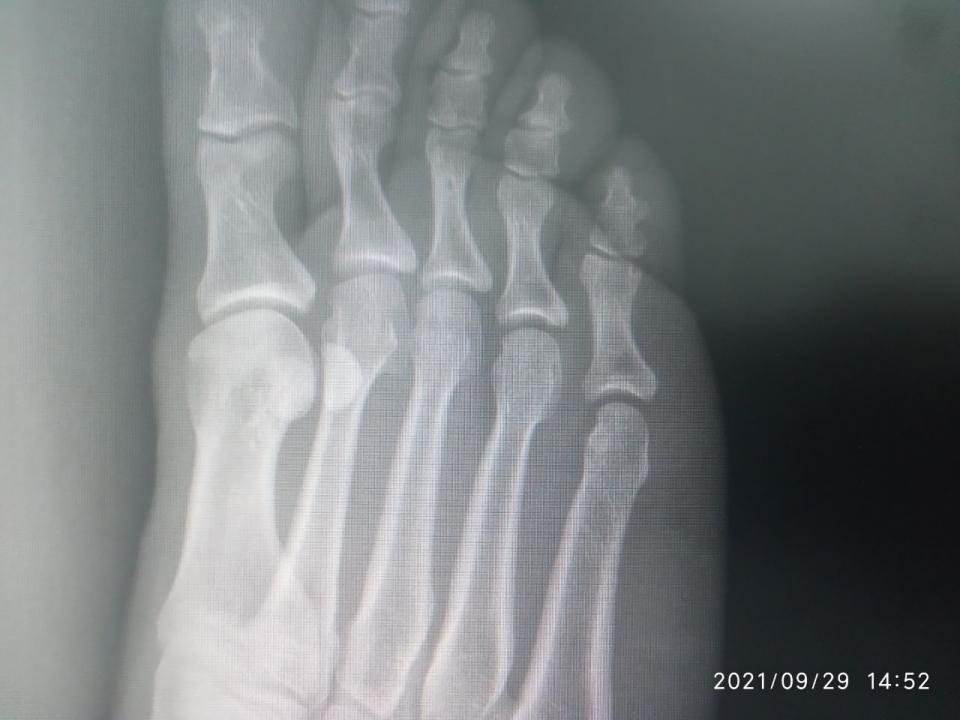

andreyyy Опубликовано 5 октября, 2021 Опубликовано 5 октября, 2021 Драсьте На фоне истощения организма, плохо заживающих ранок, падения иммунитета, что является вообще отдельной темой, не для обсуждения, я неудачно спрыгнул с брусьев. С невысоких. С собственным весом около 70 кг. Просто знаете, бывает, что не достаточно самортизировал и в стопе возникла боль при приземлении. Это было, дай бох памяти, в понедельник прошлой недели. Т.е. 8 дней назад. Сначала боль была несильная. На утро легкая, вполне себе не вызывающая беспокойства. Пошел на работу. От проходной до моего участка работы пешком далеко. Т.е. каждодневный поход н аработу - это всегда большая нагрузка в плане ходьбы. Особенно если опаздываю и иду быстрым шагом. Так я сильно мучился, когдда несколько месяцев не заживали мозоли-волдыри, нратертые обувью. Я купил эластичный бинт и перемотал стопу. По неопытности перетянул сильней необходимого. Идти стало еще больней. Шел через боль, пока боль не стала очень сильной. Остановился, размотался... К вечеру нога разболелась очень сильно. Когда говорю очень, то это буквально. Обезболился, лег спать. Проснулся утром, а боль уже невыносимая. Невозможно ступить на ногу вообще. Больно даже легонько прикоснуться пальцем к коже стопы. Я уссыкаюсь, а не могу идти. Я зову на помощь, мне несут ведро. При этом еще и морозить стало. Я измерил - 39. Напился Парацетамола, Ибупрофена, уколол 3 кубика кетанова и несколько ампул налбуфина. К последнему толерантность и он плохо действует в плане обезболивания. Зависимости нет (была), но толерантность высокая. Одна ампула вообще не дает эффекта. Как-то так. В общем, обезболился и на работу не пошел. Интенсивность боли показалась ненормальной и я поехал на такси в травмпункт. А, сначала получил направлениеп от семейной. Уже попускали лекарства, даже покачивания в такси вызывали сильную пульсирующую боль. Наступил на камушек, так заорал криком... Травмпункт отказался принимать, т.к. они работают только в первые сутки после травмы. Моя семейная такая - всю жизнь меня куда-то направляет, где говорят, что она дура и этот не к ним. Умеет только бубнеть, как сложно ей живется после реформы и как сбоит программа (просто время отклика на клик было чуть дольше чем на хорошем современном ПК, все работает четко, но она бубнит, что вот снова невозможно работать, реформа....). Короче, я там начал ругаться. Я еще нервный последнее время и на транках, которые не работают уже нихера. А шишки потерял ( Добился приема заведующего отделением. Направил на рентген. Я сфотографировал снимки на мониторе и показал ему на телефоне. Он сказал, что все пучком, все в целостности. Прописал покой, холодные компрессы, легкая намотка и капустный лист. Не шутка. А если будет болеть, немид. Если вдруг понадобится больничный, то к семейному. Вот эти "если" умиляли. Я ему же объяснил, что я несколько часов назад не мог до туалета дойти. На следующее утро та же история. В течение дня я всем чем можно обезболиваюсь, соблюдаю режим щадящий, но стоит заснуть и проснуться, как боль невыносимая и невозможно вообще даже с палочкой пройти и пару шагов. Я обнаружил, тчо кетанов не работает совсем. Вчера поставил 3 кетанова и 3 трамадола и боль ушла примерно на 60% Трамадол был последний. Оставалось на всякий случай в заначке 3 кубика. Сегодня ночью я жменями жрал пенталгин, темпалгин, ибупрофен, т.к. не хотел будить никого. Утром докупили кетанов. 2 кубика. Полнейшее отстутствие эффекта. Еще 2. Вообще ноль При этом я абсолютно уверен, что кетанов на мне работает отлично. От сильной зубной или послеоперационной боли 2 кубика снимают боль полностью. Не на долно, но полностью. Никак не связан его эффект с падением эффективности опиоидов. Я озадачен. Я не могу придумать, по какой еще причине он может не работать кроме проблем с кровообращением. С кровообращением, кстати, и правда жопа. Кончики пальцев на ногах потеряли чувтствительность. Но нога-то распухшая, кроме как кончики пальцев всюду чувствительнсоть есть. Уколол 1 налбуфин. Сижу терплаю. Дергает и пульсирует. Усомнившись в правильном ракурсе снимка, я повторно через семейного выбил направление к нашему местному травматологу. Там сделали снимог на пленку. Не знаю, как его выложить. Не могу сфотографировать, чтобы что-то было четко видно. ВЫстоял очередь к травматологу... И хорошо, что с криком "Да пошел ты " выскочил, хлопнув дверью, что штукатурка посыпалась, ибо так психанул, что если бы не выскочил, то перее..л бы его палкой (я с папиной палкой сейчас хожу), Он отказался даже смотреть снимки. К нему только по записи. По направлению нельзя. К тому же он последний день перед отпуском. Последнее он повторил несколько раз. К чему? Сейчас-то он на работе! Я стою с сильной болью, приехал на такси на одолженные деньги, а он давит лыбу и говорит, что он уже почти в отпуске и меня не примит. Ну я начал колоть диклофенак, пить Серротопептидазу. Никаких изменений. Первый рентген (цифровой) Показать Показать Показать Показать Показать Селфи Показать Селфи только что Показать Диагноз поставли "или растяжение или надрыв". Прошу совета. Я сейчас и так очень сильно погружен в решение своих других проблем и не могу много времени выделить на походы по больницам. Ждать и само заживет или что-то идет не так ? КАкие варианты ? Навскидку устрпоит. Вообще чтоб понимать, что МОЖЕТ быть. Чем обезболиваться ? Я не могу вспомнить хороший нецентрального действия преп, который тоже хорошо помогает в плане обезболивания (чуть ли не на уровне кетаролака). Что из сильного ненаркотического ? буду пробовать все.